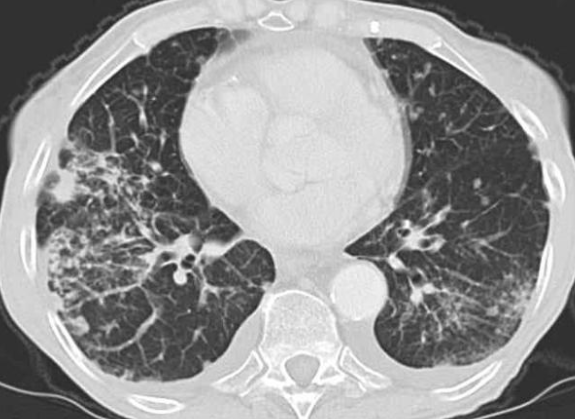

CT

- Epaississements irréguliers des septas

- Epaississements péri-bronchovasculaires